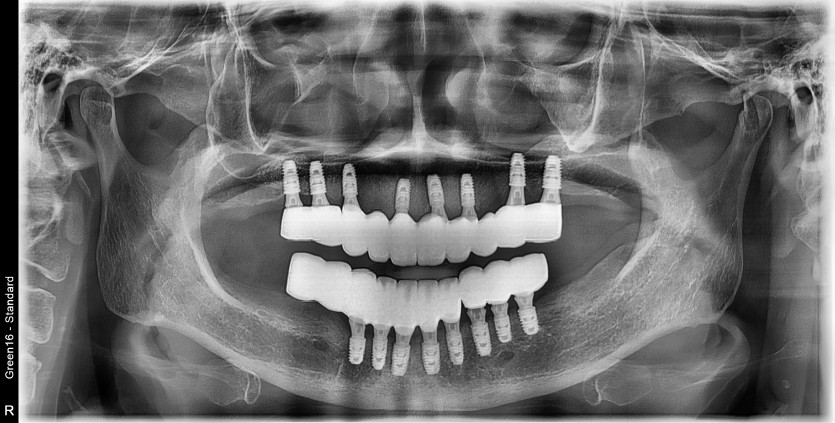

만 65세 전체 임플란트 증례

전체 임플란트 증례입니다.

16개의 임플란트로 완성하였습니다.